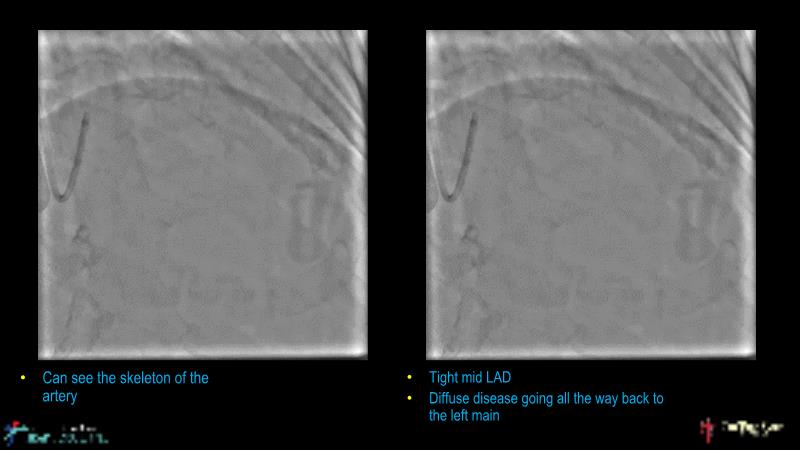

• To understand why the use of IVUS imaging is different from seeing with experienced eyes to achieve improved left main bifurcation outcome